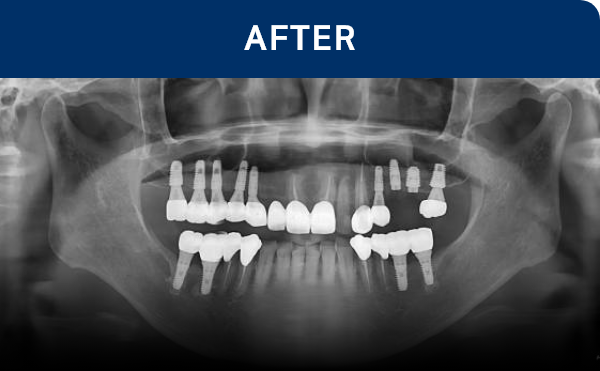

清晰可见的成果,

就是新吉种植牙

科值得信赖的证明.

通过种植牙, 让您无忧进食, 自在微笑, 重拾生活的舒适感